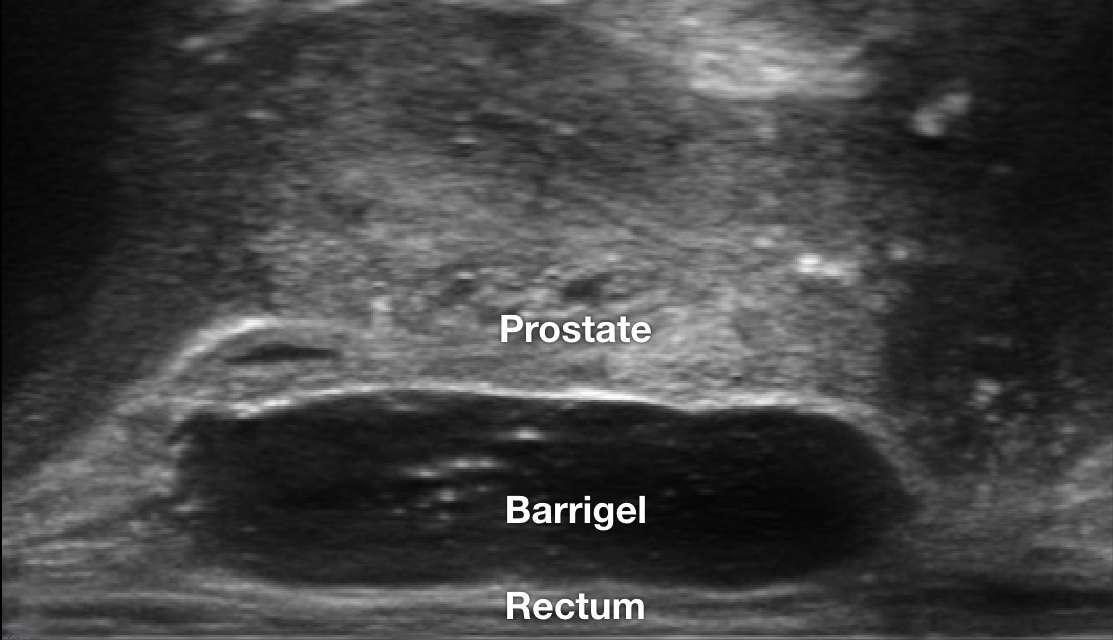

TRUS IMAGES

TRUS image courtesy of Neil F. Mariados, MD

Radiation Oncologist; New York, United States